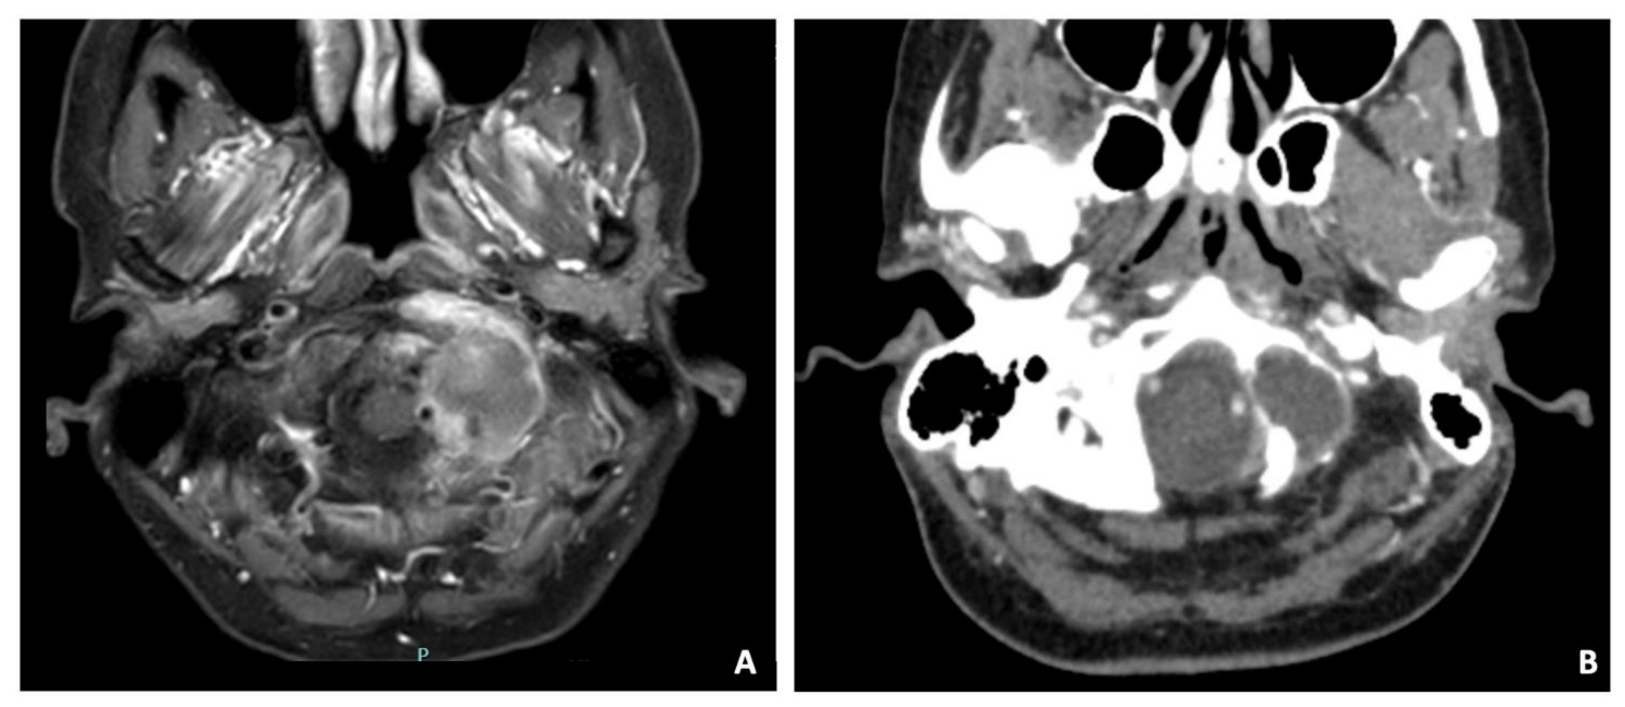

3.1. Case 1—Clival Osteoradionecrosis

| 1 | 36 | M | Drowsiness, cephalea, fever and aqueous rhinorrhea | EEA | Biopsy and CSF leak repair | Osteoradionecrosis | None | Yes | 36 months | Dead |